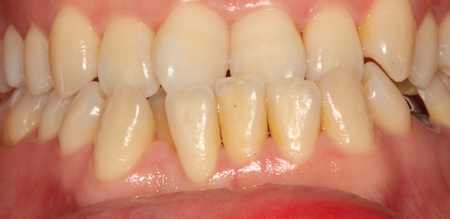

치주염 (중기~말기)

주기적으로 잇몸이 붓고 피가 나며, 욱씬하거나 우리한 통증이 나타남.

치주치료 및 정도에 따라 치주수술(잇몸수술)이 필요함. 향후 관리 정도에 따라 3~6개월 간격으로 내원하여 유지치료를 시행하여야 함.

치주염 (말기)

잇몸이 항상 부어 있으며, 이가

흔들리는 정도가 점점 심해짐.

치주치료가 필요하며, 정도에 따라 치아를 발치하여야 할 수 있음.

치주치료 전후사진

B

A